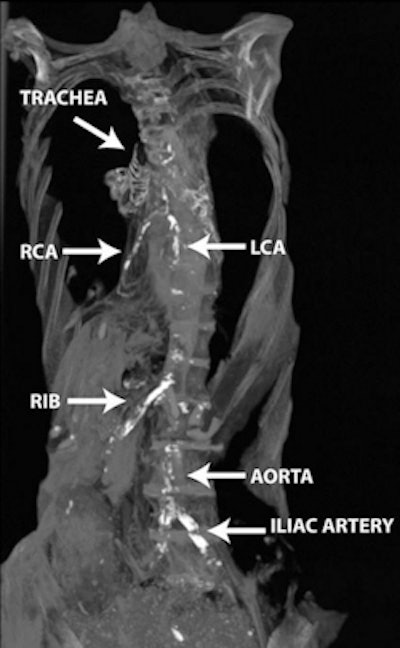

The study team scanned 178 consecutive modern Egyptian patients, all of whom had been referred by their primary physicians for cancer staging with PET at the Alfa Scan Outpatient Radiology center in Cairo. All patients were scanned on a Gemini TF PET/CT scanner (Philips Healthcare) in a single session from the base of the skull to the knee. Images were acquired using 1-mm slices and an average time interval of 0.8 msec. Interpretation consisted of searching for vascular calcifications in different vascular beds.

These results were compared with whole-body CT scans of 76 Egyptian mummies (3100 B.C.E. to 364 C.E.) scanned for the 2011 publication on a six-detector-row Emotion 6 scanner (Siemens Healthcare). Five experienced cardiovascular imaging physicians among the Horus investigators (who also performed the living human study) looked for cardiac and vascular calcifications in the carotid, coronary, aortic, iliofemoral, and peripheral vascular beds. Mummy selection was based on the specimens being in a good state of preservation rather than on random selection, the study team noted.

In both ancient and modern populations, "vascular calcification starts at the peripheral vascular bed (iliofemoral then aortic beds), then spreads to the target vessels (coronary and carotid beds) around a decade later than the onset of aortoiliac calcification," the authors wrote. There was also a trend toward higher incidence of vascular calcification among female mummies, but not modern Egyptians. Allam and colleagues hypothesized that the women may have been exposed to household smoke.